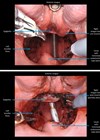

Robotic surgery for squamous cell cancer: the new frontiers

Although the da Vinci platform was FDA approved for early-stage oropharyngeal cancers, the indications have expanded. In this article, John Hardman explains how surgeons, with greater understanding of the strengths and limitations of robotic surgery, have systematically set out to...